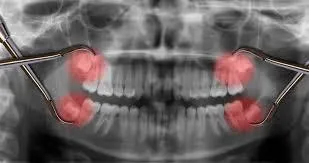

#10 - Wisdom Teeth Become Inflamed

Wisdom teeth are tricky business. They seem to come whenever they please, and when they do, they can easily wreak havoc. Pericoronitis is an infection that can occur when your wisdom teeth don’t come in properly. If you get it, you’ll know because of your irritated gums in that area, as well as possible bad breath. See a dentist as soon as possible to get this one figured out.